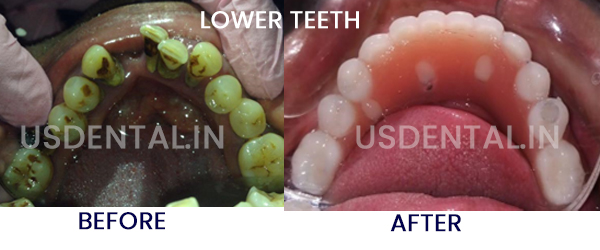

How to Deal with Pyorrhea? Patient has visited us with the chief complaint of multiple upper and lower loose teeth.…

How to Deal with Pyorrhea? Patient has visited us with the chief complaint of multiple upper and lower loose teeth.…